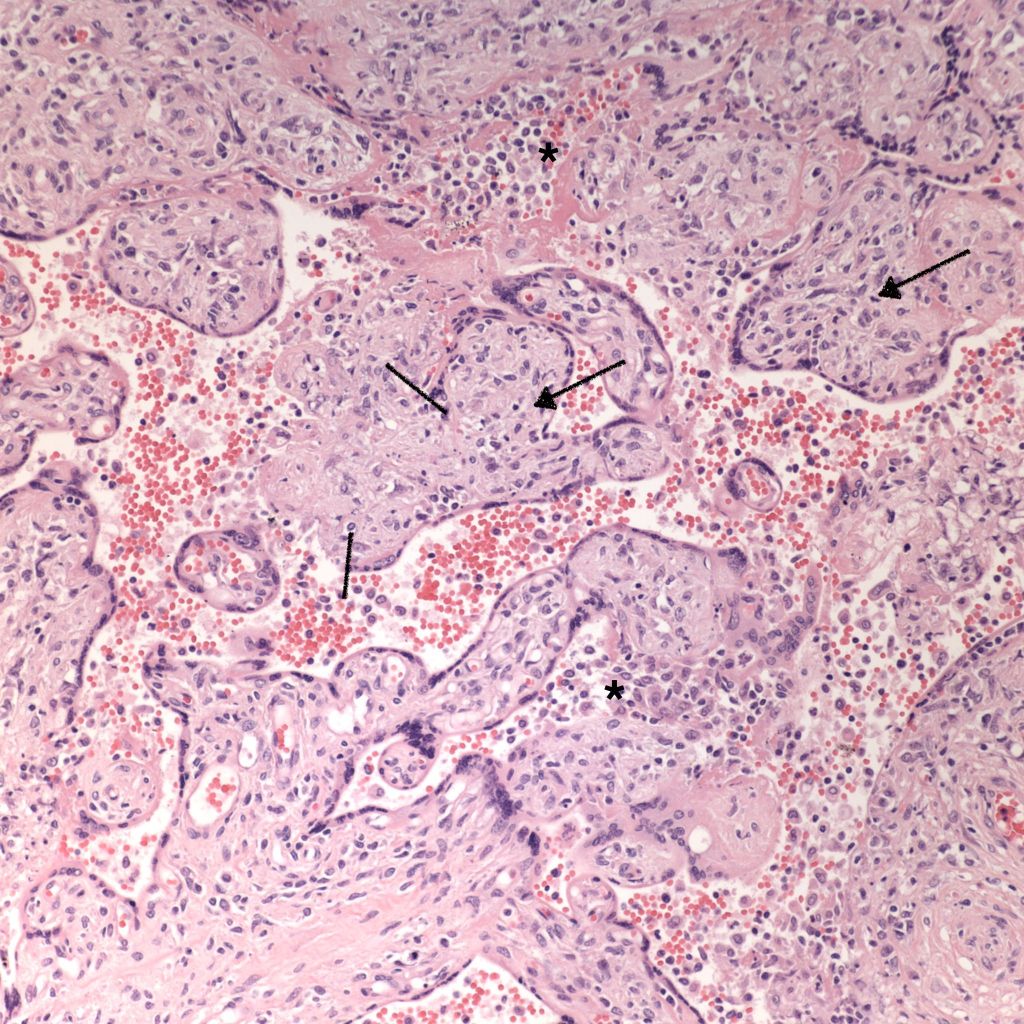

High Grade (massive) CHIV

Microscopic criteria: The primary criterion is monocytes clustered in the intervillous space which can be confirmed by CD 6810,17. The monocytes often have kidney bean shaped nuclei and prominent cytoplasm. Some other consensus criteria are that the inflammatory cells in the intervillous space should be at least 80% monocytes, and these should be maternal cells1,17.

Extent and Severity: If this is an untreated case, one accepted criterion is that the monocytes occupy 5% of the sampled intervillous space. The severity can also be graded usually as less than versus more than 50% of the intervillous space filled with monocytes. The number of monocytes in the largest clusters, and whether the distribution is evenly distributed or focal may also be useful observations.